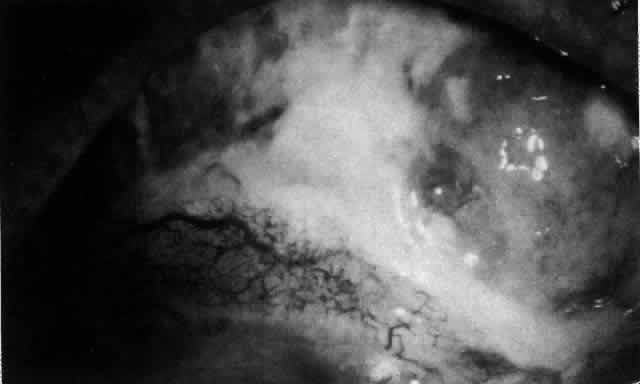

The characteristic features of necrotizing scleritis on fluorescein angiography are hypoperfusion and, eventually, nonperfusion of the vascular networks (Figs. 40 through 43).26 The initial changes are on the venous side of the capillary network; the transit time of the dye increases even if the eye is red and congested. If the disease process persists or has been present for a long time, thrombosis and permanent vaso-occlusive changes occur. These vessels (or the occluded capillary network) are bypassed by the opening of anastomotic channels. New vessels in a granuloma give rise to deep intrascleral leakage of dye (see Fig. 43). Conjunctival and episcleral involvement by the destructive change is late but is always preceded by vaso-occlusive changes that can sometimes be detected with use of the red-free light on the slit lamp (Figs. 44 and 45).